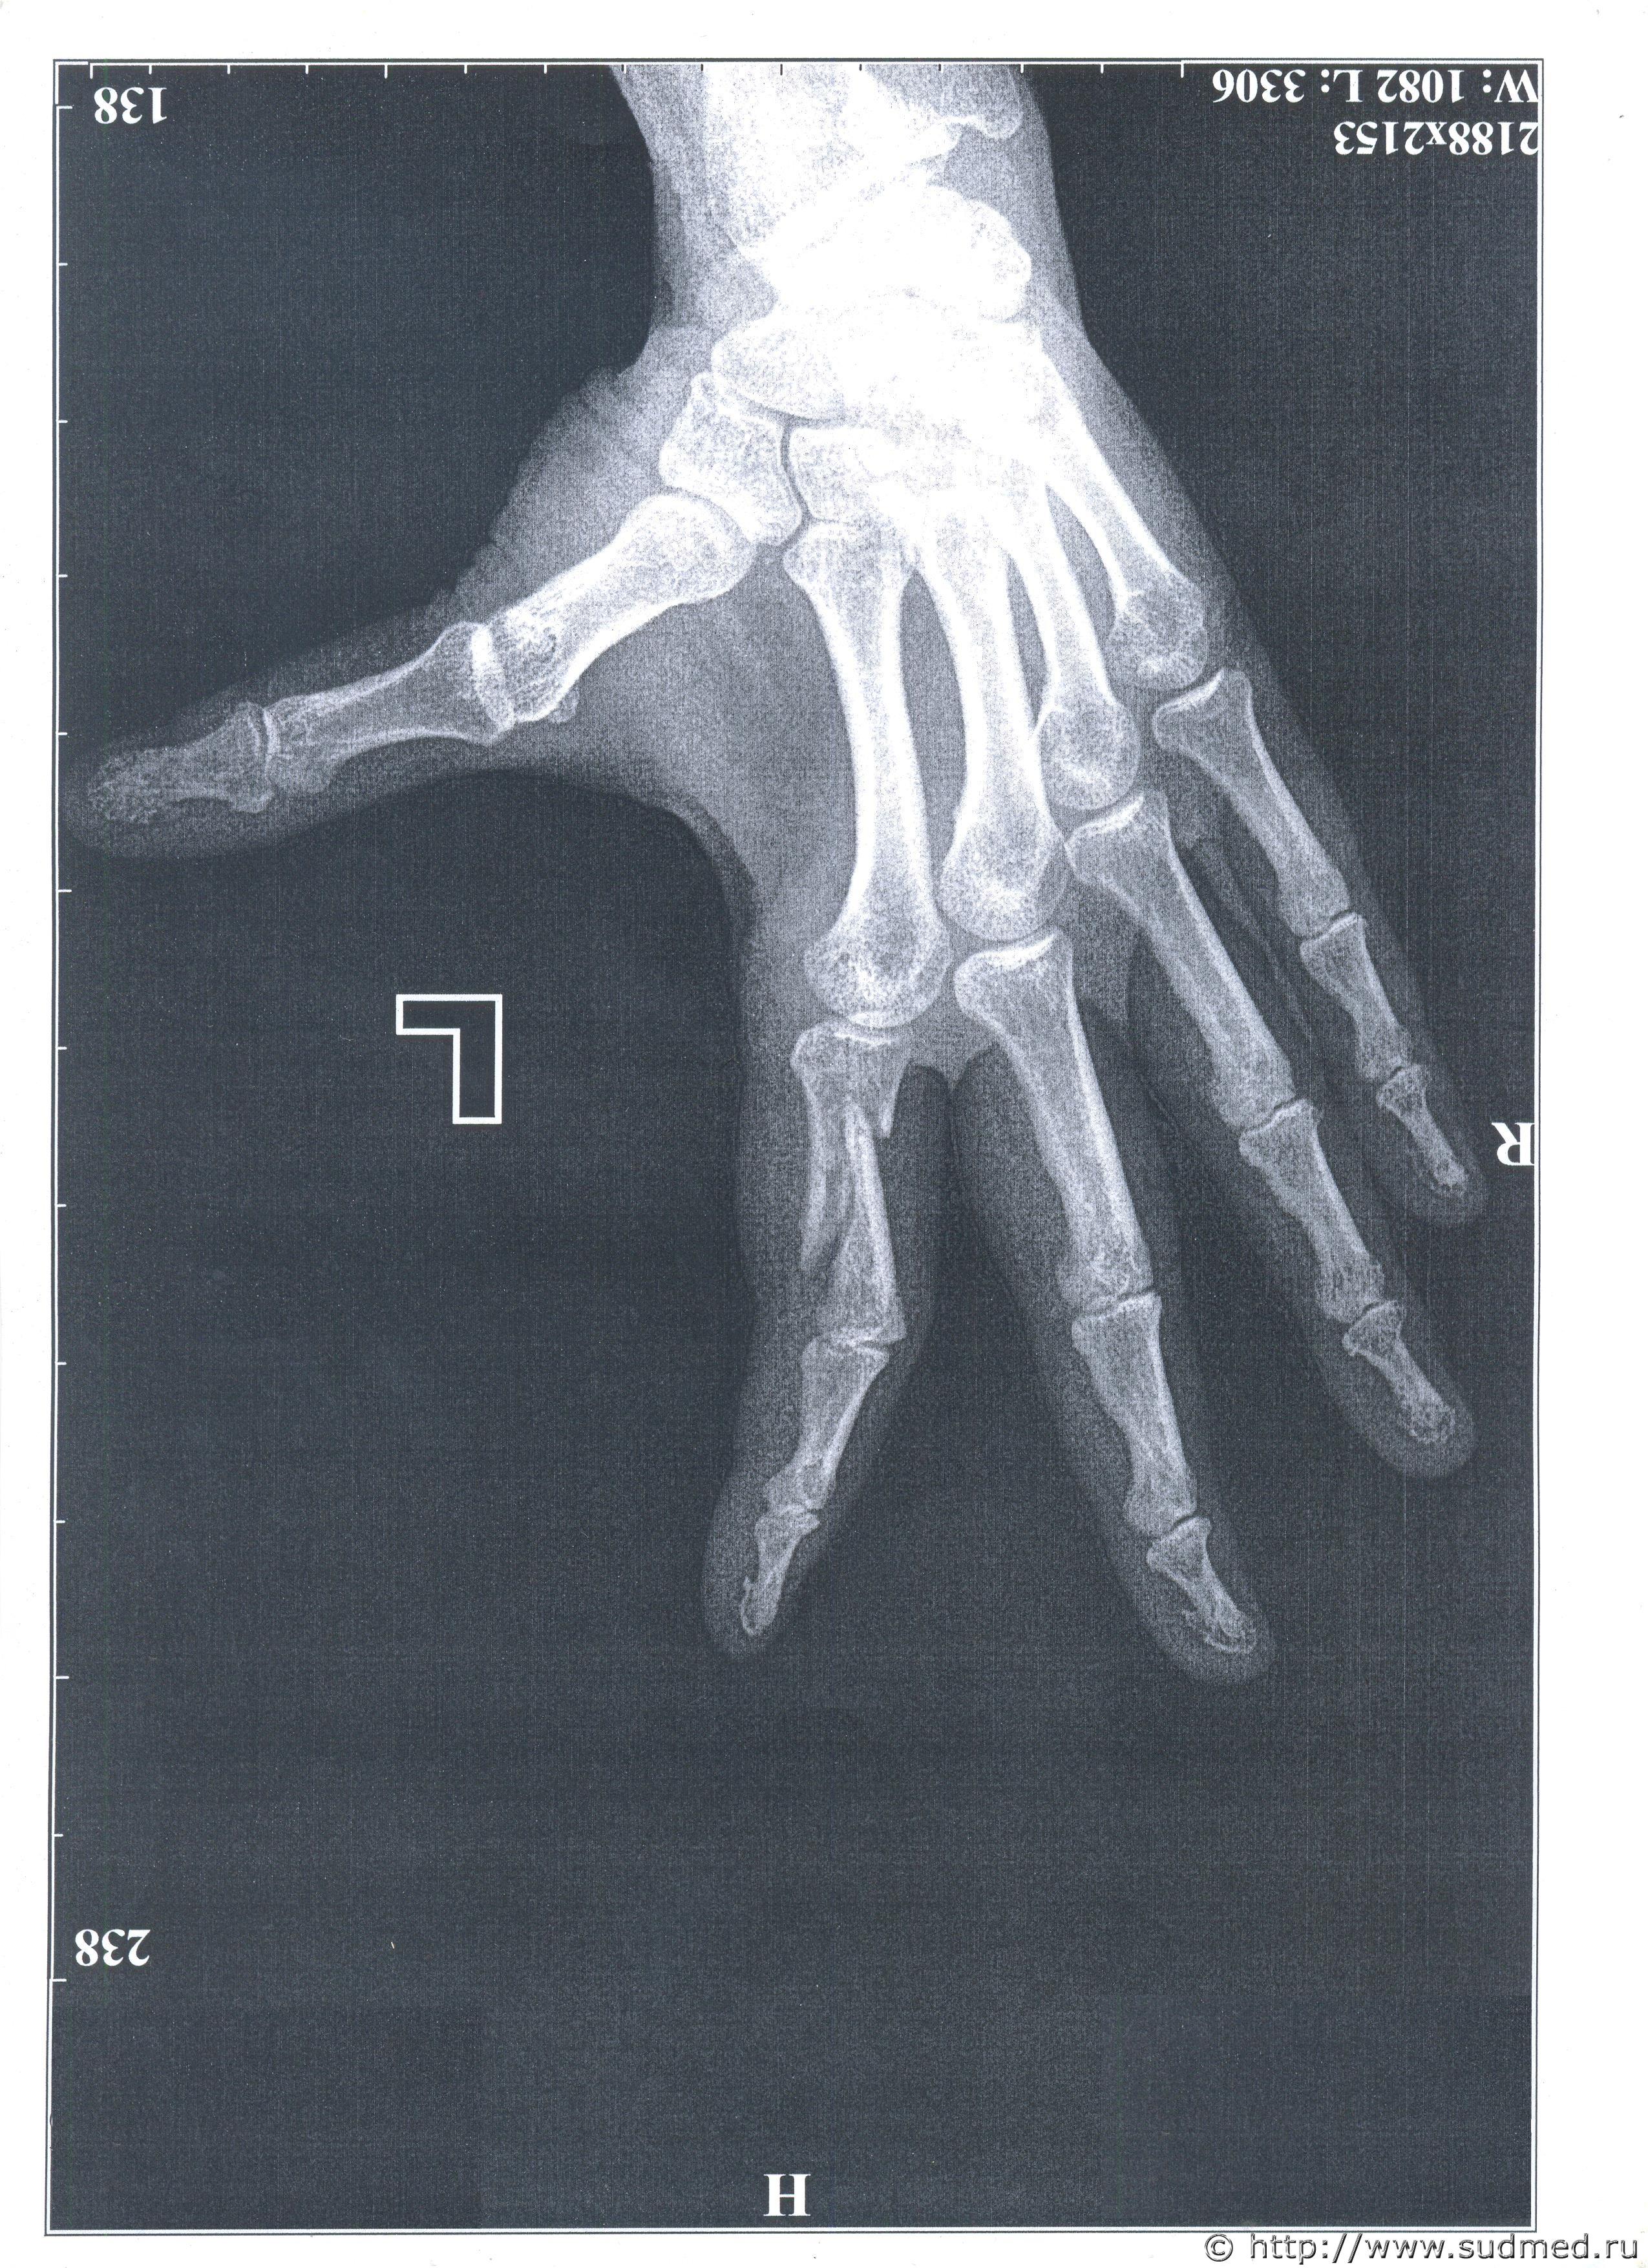

Добрый день. Как именно нужно упасть, что бы поломать палец таким образом. Падение из положения стоя. Оскольчатый перелом со смещением. Я - потерпевшая, закрывала голову рукой, по которой били пивной кружкой. Ответчик с адвокатом утверждают, что я упала таким образом. Заранее спасибо.Судебная медицина - Прикрепленное изображение Судебная медицина - Прикрепленное изображение

Работа у адвокатов такая - за деньги подонкам помогать. То что они говорят, абсолютная чушь. На снимке совершенно очевидно,что такой перелом не мог образоваться от осевой нагрузки, а "упасть" и получить такое действительно сложно. Пусть детально соврут, подпишут, и потом через ходатайство потребовать поставить вопрос эксперту об установлении механизма образования перелома и возможности его получения при обстоятельствах и по механизму указанного подозреваемым (а в конце - если возможно и при обстоятельствах указываемых пострадавшей - то по какому механизму наиболее вероятно). Уверен, бредовую идею о падении, даже среднего уровня медицинский криминалист разобьет в легкую.

Формирование оскольчатого перелома характерно для ударного воздействия тупого твердого предмета в проекции перелома. Так, как Вы написали, т.е. от удара кружкой по основной фаланге указательного пальца, который был прижат к голове, этот перелом вполне мог возникнуть. Хрестоматийный пример. При падении такой перелом мог бы образоваться только при стечении ряда уникальных обстоятельств. При падении с упором на ладонь или на кончик указательного пальца такой перелом принципиально не может образоваться.

Добры день, уважаемые эксперты. Был перелом руки. Прикрывала голову рукой,а по ней ударяли кружкой. Подозреваемый выдвинул версию, что я упала так, потом обогатил ещё тем, что я так махала рукой, что могла задеть за стол или его пивную кружку - и поломать руку.Прикладываю рентген и выдержки из двух экспертиз. Очень большая просьба объяснить - что такое

1) "действие травмирующей силы по оси пальца"

2) " контактный ПРЯМОЙ удар"

И ещё очень непонятна фраза - "установленный перелом мог образоваться при любых условиях, допускавших контактное взаимодействие поврежденной фаланги пальца и поверхности травмирующего предмета" - тут понятно, что естественно, если хорошо размахнуться- то можно - но степень "хорошо" должна быть определенная.

"По оси пальца" - то есть вдоль самого пальца (удар кончиком выпрямленного пальца или по кончику пальца - как, например, с большой силой "ткнуть" выпрямленным пальцем в стену или т.п., либо сильно ударить чем-то по выпрямленному пальцу - нередко в баскетболе так бывает, когда неудачно приходит мяч) или вдоль оси основной фаланги, если палец согнут.

"Контактный прямой удар" - ударное воздействия тупого твердого предмета в проекции перелома. Именно то, о чем Вы пишите - удар пивной кружкой по месту перелома, когда палец лежал на голове.

Прочность основной фаланги указательного пальца сопоставима с прочностью куриной бедренной кости. Если не лень экспериментировать, то можете попробовать самостоятельно оценить достаточность условий для её перелома: это явно не "обычное" эмоциональное размахивание руками.